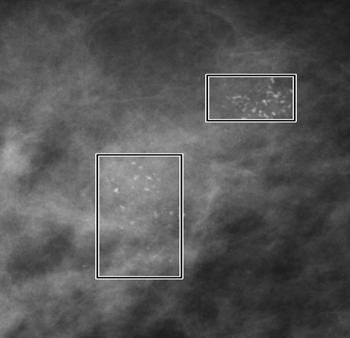

| Microcalcifications (above) within the rectangular frames show the extent the calcifications that are detected by CAD. Masses (below), architectural distortions, and focal asymmetries are marked with the circular frame. Images courtesy of iCAD. |